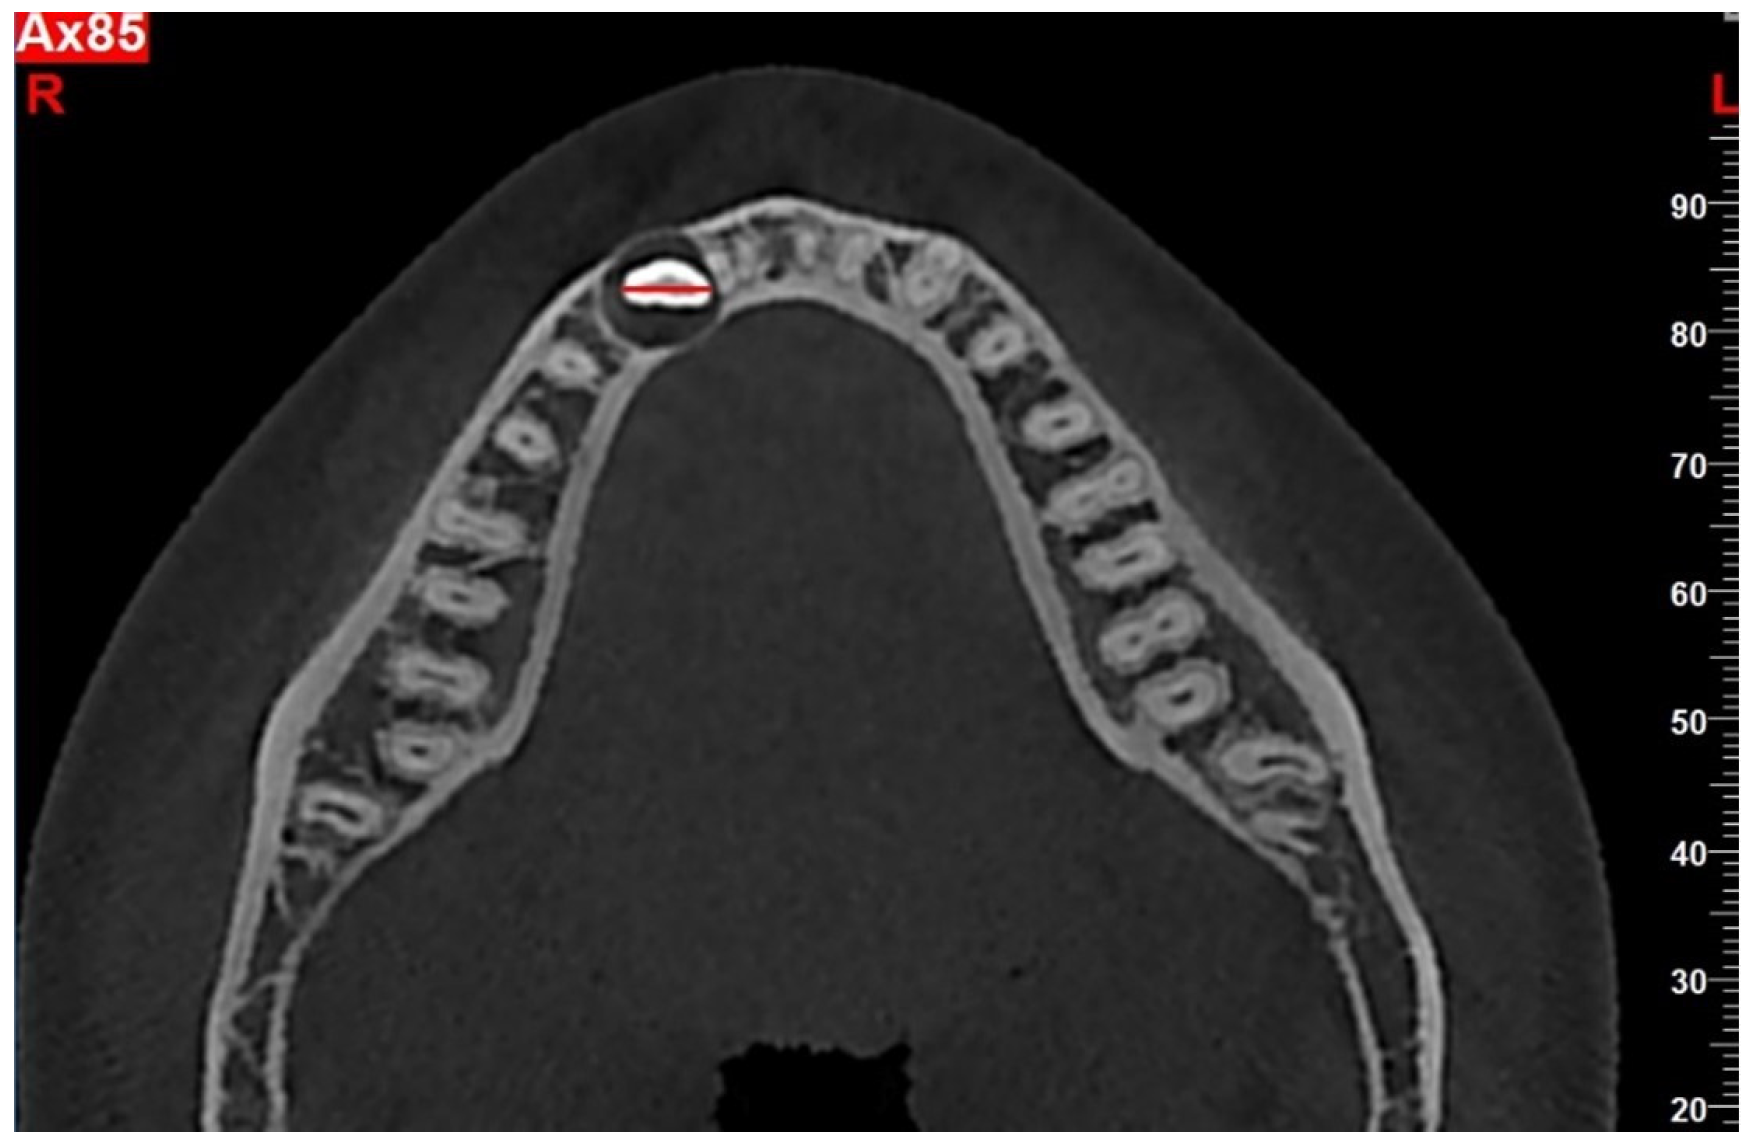

| Cortical bone perforation | No | 9 (16.7) |

| Labial | 29 (64.4) | |

| Lingual | 12 (26.7) | |

| Labial and lingual | 4 (8.9) | |